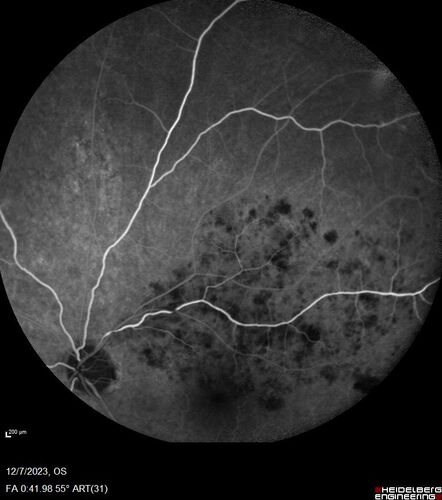

BRVO with good vision

87 year old man with good vision (diabetes without retinopathy). VA 20/25 OU. Vision never worsened from BRVO OS.